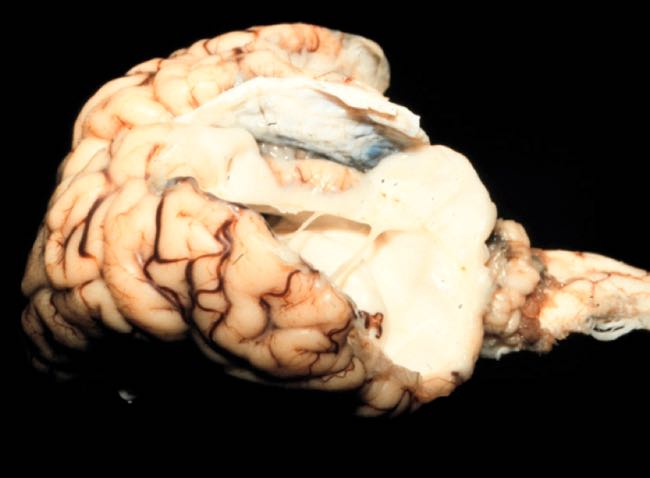

The biggest problem with the virus is however that it crosses the placenta to affect the growing foetus in pregnant animals. The most susceptible stages of pregnancy for foetal deformities are days 62-180 in cattle and 25-50 in sheep (older foetuses can clear the virus themselves). Effects on early stages of pregnancy are not clear at this stage. The virus damages foetal nerve tissue and results in brain and spinal cord abnormalities with secondary problems with the muscles and skeleton leading from the nerve damage.

In newborn animals and foetal sheep, goats and cattle, the disease is associated with animals born alive or dead at term or aborted following infection of the dam. Malformations observed include bent limbs and fixed joints, which may be all limbs and spine or only some limbs or joints, brain deformities (hydranencephaly) and damage to the spinal cord. Persistent flexion/fusion of the joints (arthrogryposis or 'contracted tendons') is a very common birth defect with Schmallenberg virus. Some animals are born with a normal appearance but have nervous signs such as a 'dummy' presentation (blindness, ataxia, recumbency, an inability to suck, and sometimes seizures). The foetal deformities vary depending on when infection occurred during pregnancy. In sheep there may be only one lamb out of a multiple birth affected, with the others normal.